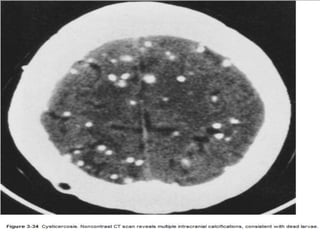

Neurocysticercosis

– Larval form of T. solium – cysticercus cellulosae

– Most common CNS parasite

– location

• Subarachnoid space

• Brain parenchyma- corticomedullary junction

• Intraventricular in 20-50% cases

– Dying larva incite host inflamatory reaction &

calcifies later

Pathological stages

(over 1-9 yrs; 5 yrs in average)

• 4 stages of development, healing, regression

– Vesicular (viable larva): Cyst + scolex

– Colloidal vesicular (dying larva): Intense

inflammation, edema

– Granular nodular (healing): Cyst involutes, edema

diminishes

– Nodular calcifying (healed): Quiescent fibrocalcified

nodule

Imaging

– Vesicular: Cyst with “dot” (scolex), no edema, no

enhancement. (MRI - cyst is isointense to CSF and scolex is

isointense to white matter)

– Colloidal vesicular: Ring enhancement, edema

striking Cyst contents hyperintense on T1- and T2-weighted images

(proteinaceous fluid), cyst wall is thick and hypointense)

– Granular nodular: Faint rim enhancement, edema

decreased

– Nodular calcified: CT Ca++, MR “black dots”

(**Common to have lesions in different stages)